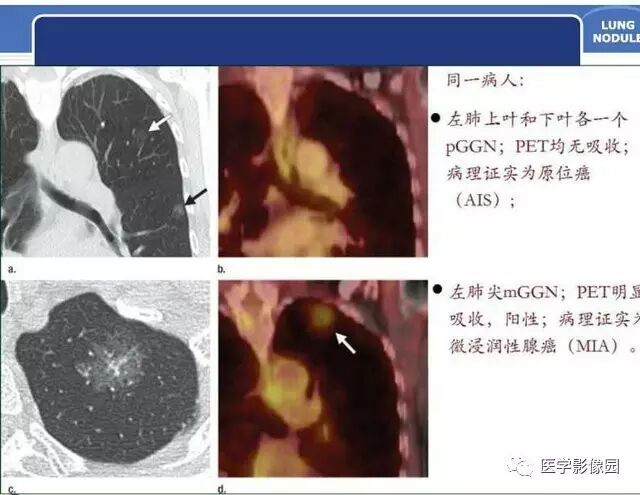

肺磨玻璃结节的CT诊断与临床处理策略